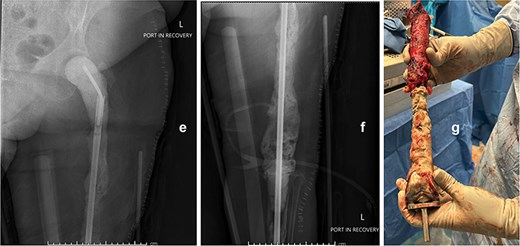

Seven days later, reimplantation was performed. A press-fit cup with a dual mobility liner was placed in the acetabulum to reduce dislocation risk. A modular TFR system was used: proximally, a femoral stem compatible with the dual mobility head; distally, a rotating-hinge knee mechanism attached to a tibial stem. Soft-tissue reconstruction was performed as feasible. The wound was closed over a drain and protected with a negative-pressure dressing. The patient remained non-weight-bearing with a knee immobilizer and continued intravenous cefazolin postoperatively for six weeks.

Postoperatively, early imaging confirmed appropriate implant alignment. Motor function was preserved, and the incision healed without complication. She began a structured rehabilitation program with gradual progression to protected ambulation using an orthotic knee brace. At follow-up, the patient demonstrated functional limb

use, no signs of recurrent infection, and a stable prosthesis without evidence of hardware failure (Fig. 3).

The modular TFR implant (h) is grossly visualized prior to implantation. Immediate postoperative anteroposterior (i and j) and lateral (k and l) radiograph following definitive reimplantation, showing the modular total femur replacement with a dual mobility acetabular component proximally and a rotating-hinge knee mechanism distally in appropriate alignment.